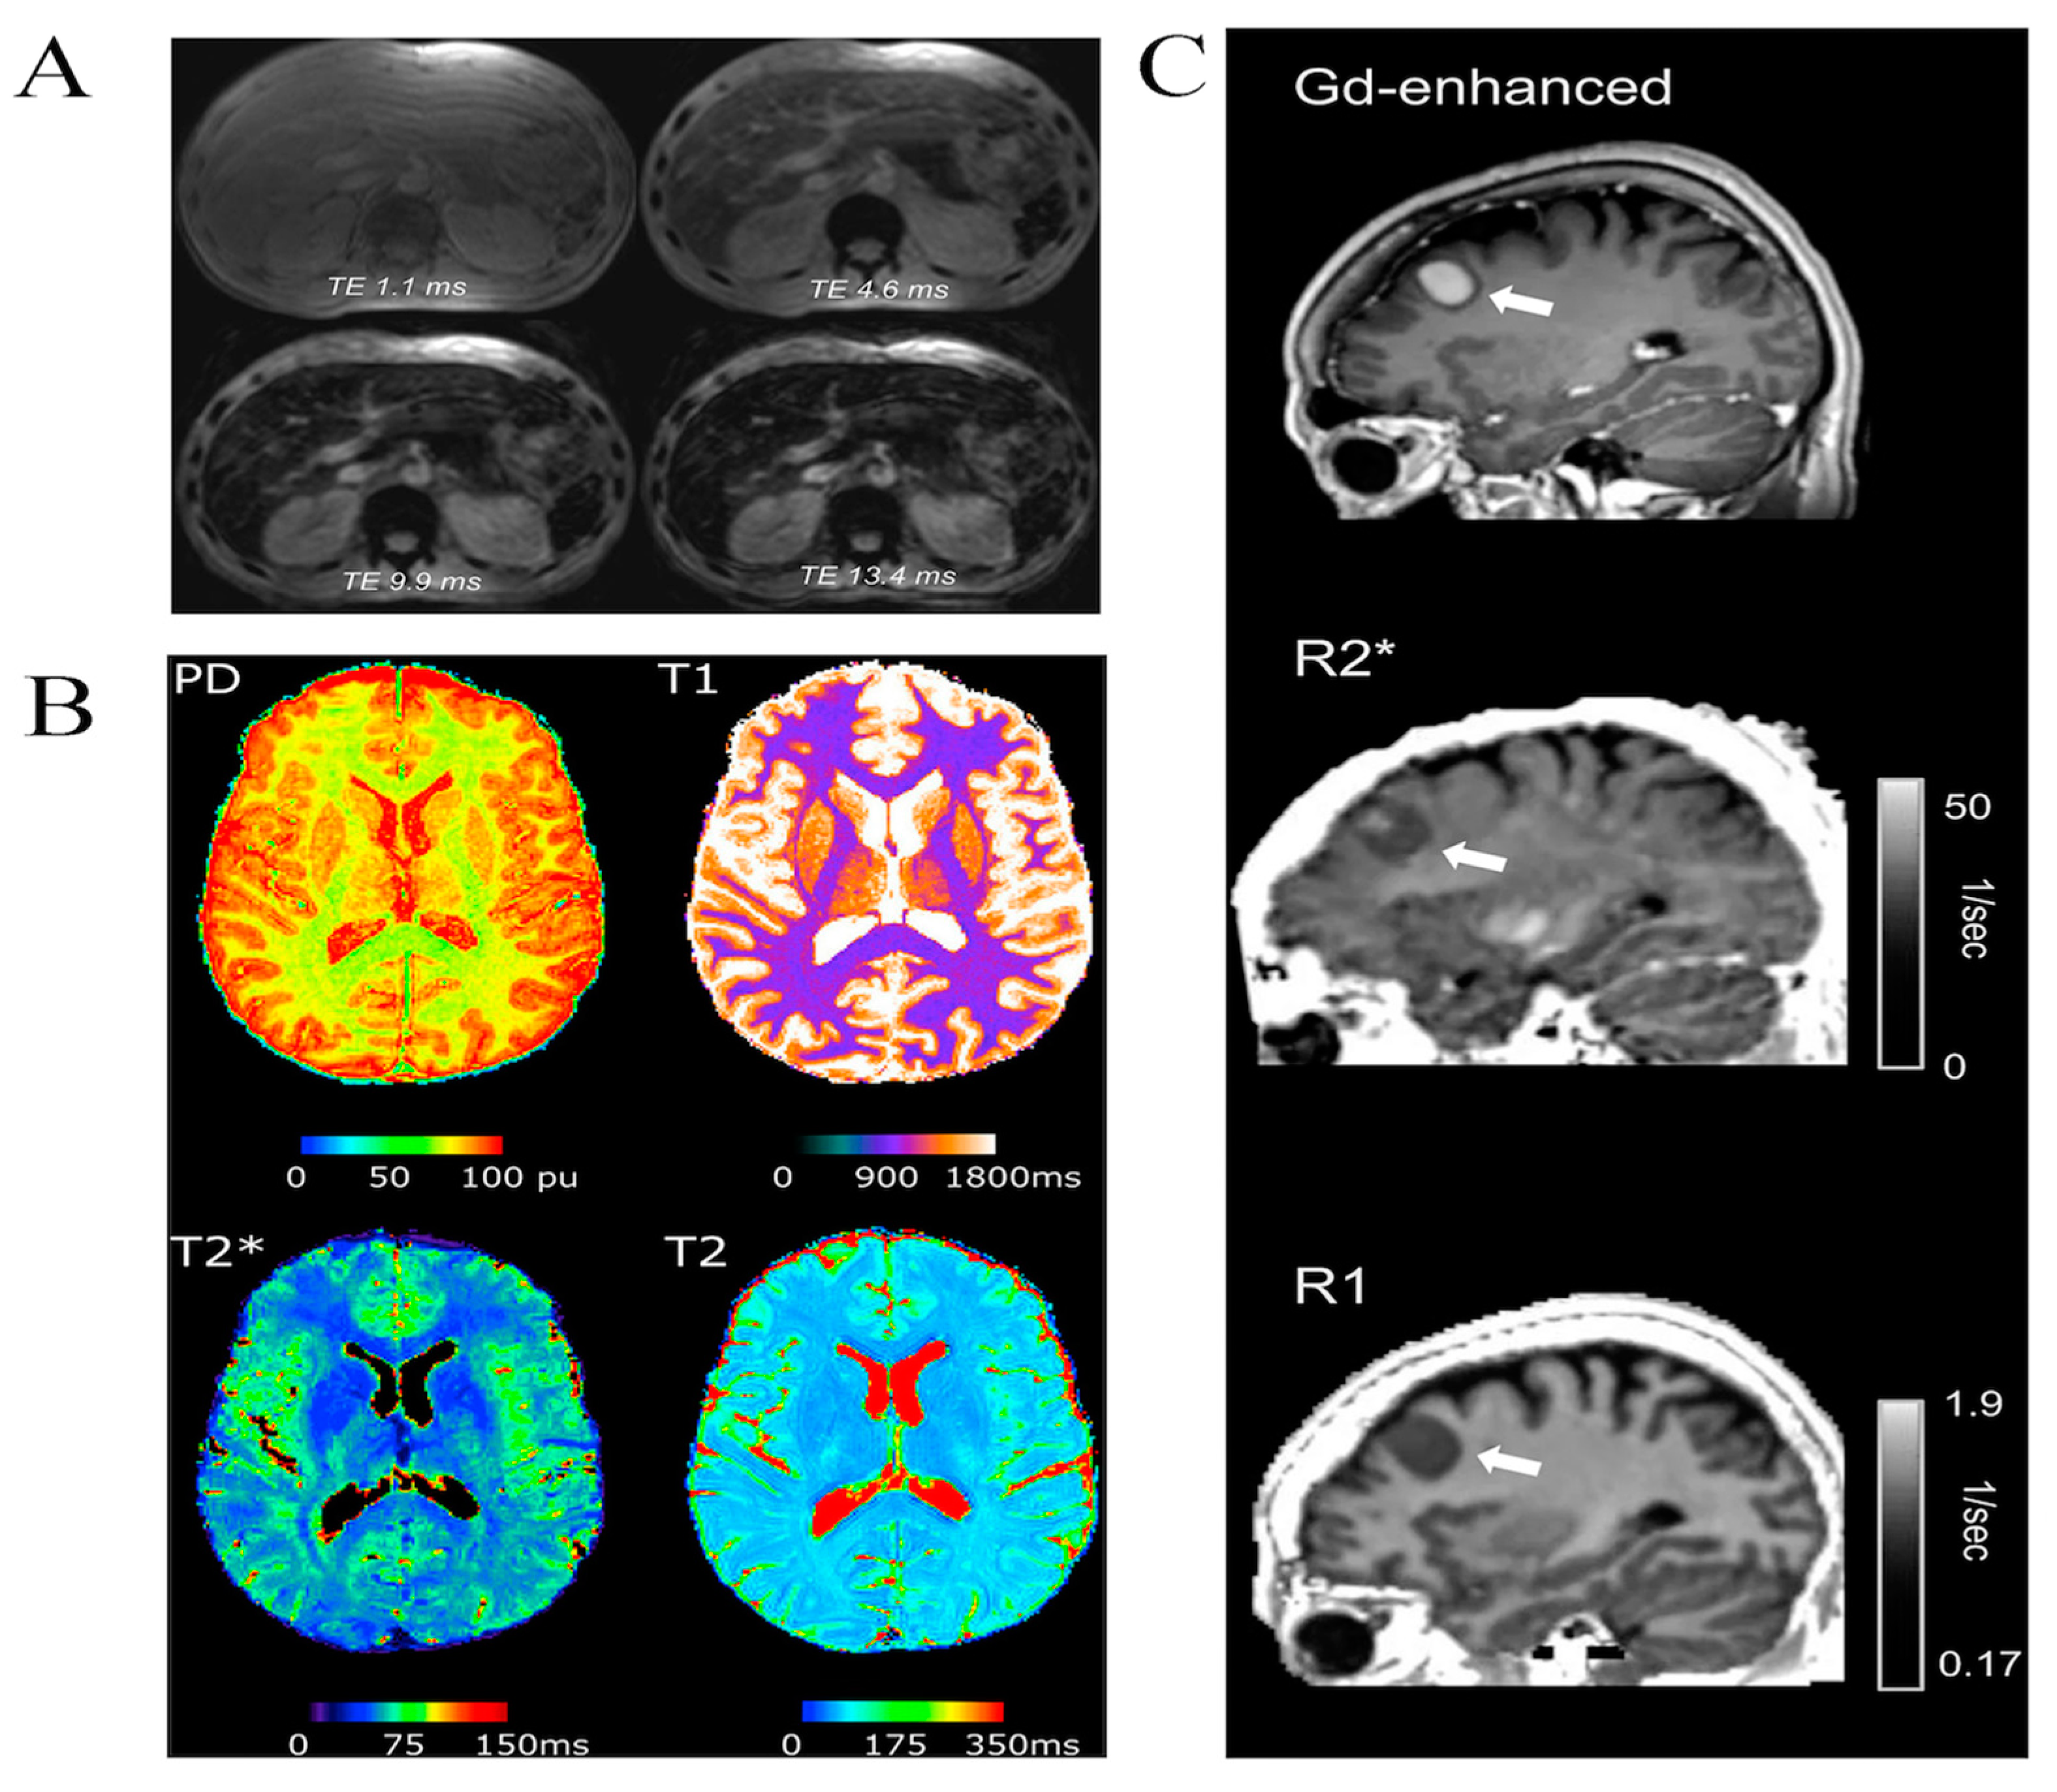

- Cashmore, M.T.; McCann, A.J.; Wastling, S.J.; McGrath, C.; Thornton, J.; Hall, M.G. Clinical quantitative MRI and the need for metrology. Br. J. Radiol. 2021, 94, 20201215. [Google Scholar] [CrossRef]

- Gracien, R.-M.; Maiworm, M.; Brüche, N.; Shrestha, M.; Nöth, U.; Hattingen, E.; Wagner, M.; Deichmann, R. How stable is quantitative MRI?—Assessment of intra- and inter-scanner-model reproducibility using identical acquisition sequences and data analysis programs. NeuroImage 2020, 207, 116364. [Google Scholar] [CrossRef]

- Filo, S.; Shaharabani, R.; Bar Hanin, D.; Adam, M.; Ben-David, E.; Schoffman, H.; Margalit, N.; Habib, N.; Shahar, T.; Mezer, A.A. Non-invasive assessment of normal and impaired iron homeostasis in the brain. Nat. Commun. 2023, 14, 5467. [Google Scholar] [CrossRef]